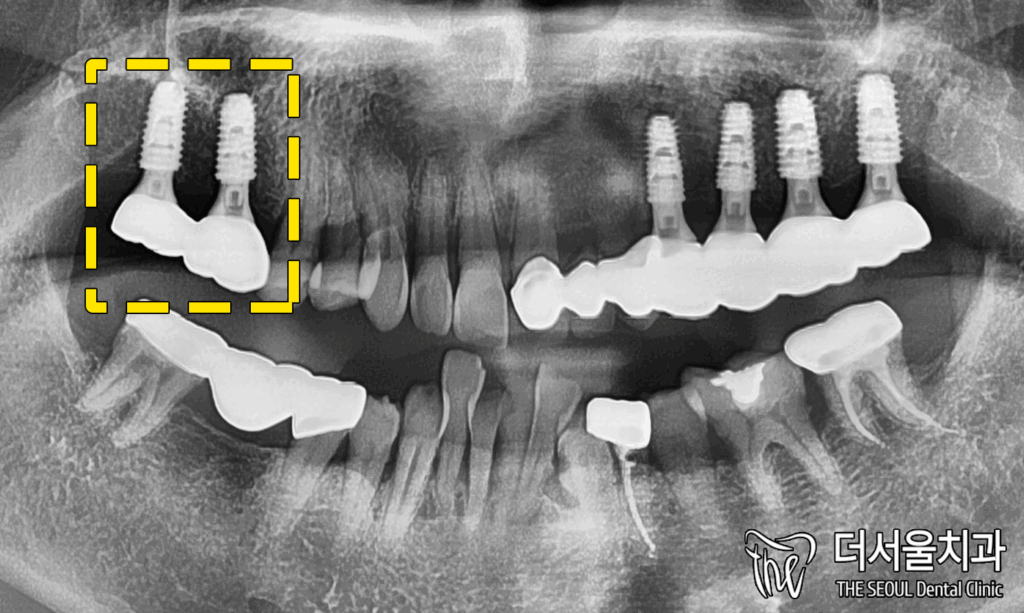

4. 완료

오른쪽 역시 최종 세팅을 하기에

적합한 ISQ 수치를 가졌습니다.

확인이 끝난 뒤

맞춤형 보철 제작에 들어갔으며,

최종 세팅이 끝남에 따라

모든 임플란트 수술은 끝났습니다.

성남 치과에 처음 오셨을 때와

구강 상태가 많이 달라졌죠?

훨씬 더 나은 모습을 보여주고 있습니다.

교합면을 살펴봤을 때도 마찬가지죠.

이렇게 모든 치료 과정은 다 끝났습니다.